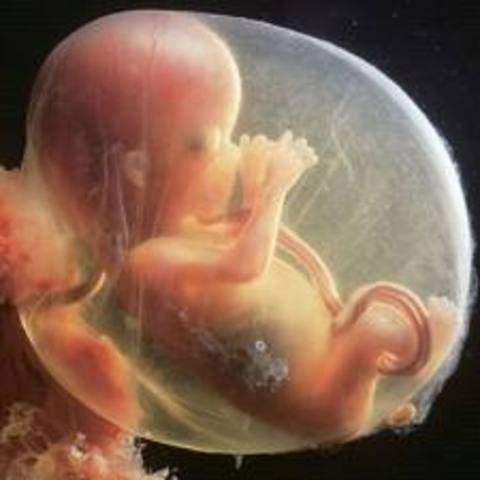

After 8 weeks the embryo becomes known as a fetus.

The yolk sac goes away and the placenta is used, which is the fetus’s life support.

The fetus spends 90% of the time in the womb sleep and the other 10% awake.

The fetus has been known to have REM sleep which means that it could be dreaming